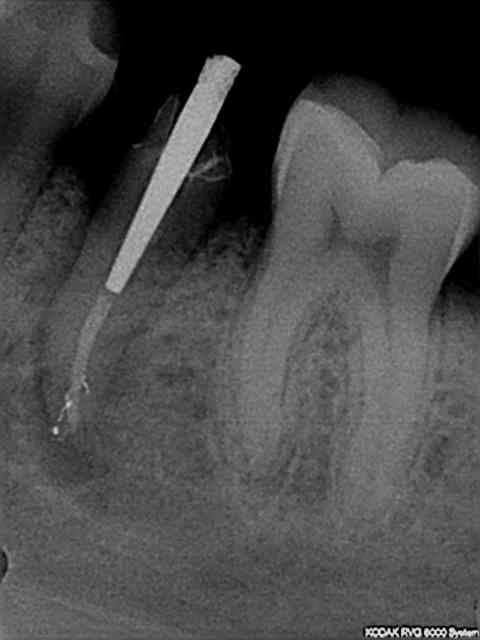

Sans problème, mais voici aussi la radio de controle du premier cas.

L'autre cas date d'hier soir une 45 non infectée mais fracturée.

Pas de canaux latéraux mais une obturation aisée avec juste un petit dépassement de ciment.